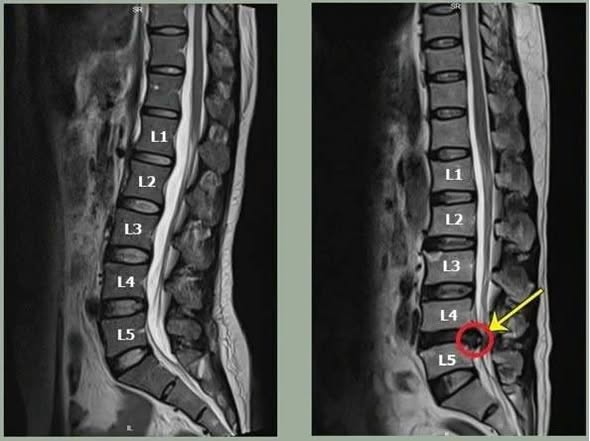

Tóm lại, thoát vị đĩa đệm ở cột sống thắt lưng là một bệnh lý rất phổ biến và nếu không được điều trị kịp thời có thể gây ra nhiều biến chứng nghiêm trọng. Nhờ vào phương pháp chẩn đoán tiên tiến như chụp cộng hưởng từ MRI, các bác sĩ có thể xác định chính xác tình trạng bệnh và lựa chọn phương pháp điều trị thoát vị đĩa đệm cột sống thắt lưng phù hợp, mang lại hiệu quả cao. Vì vậy, bệnh nhân hoàn toàn có thể yên tâm rằng việc điều trị càng sớm sẽ giúp cải thiện kết quả điều trị và giảm thiểu các rủi ro.